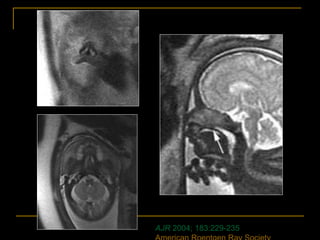

Embryology

AJR 2004; 183:229-235